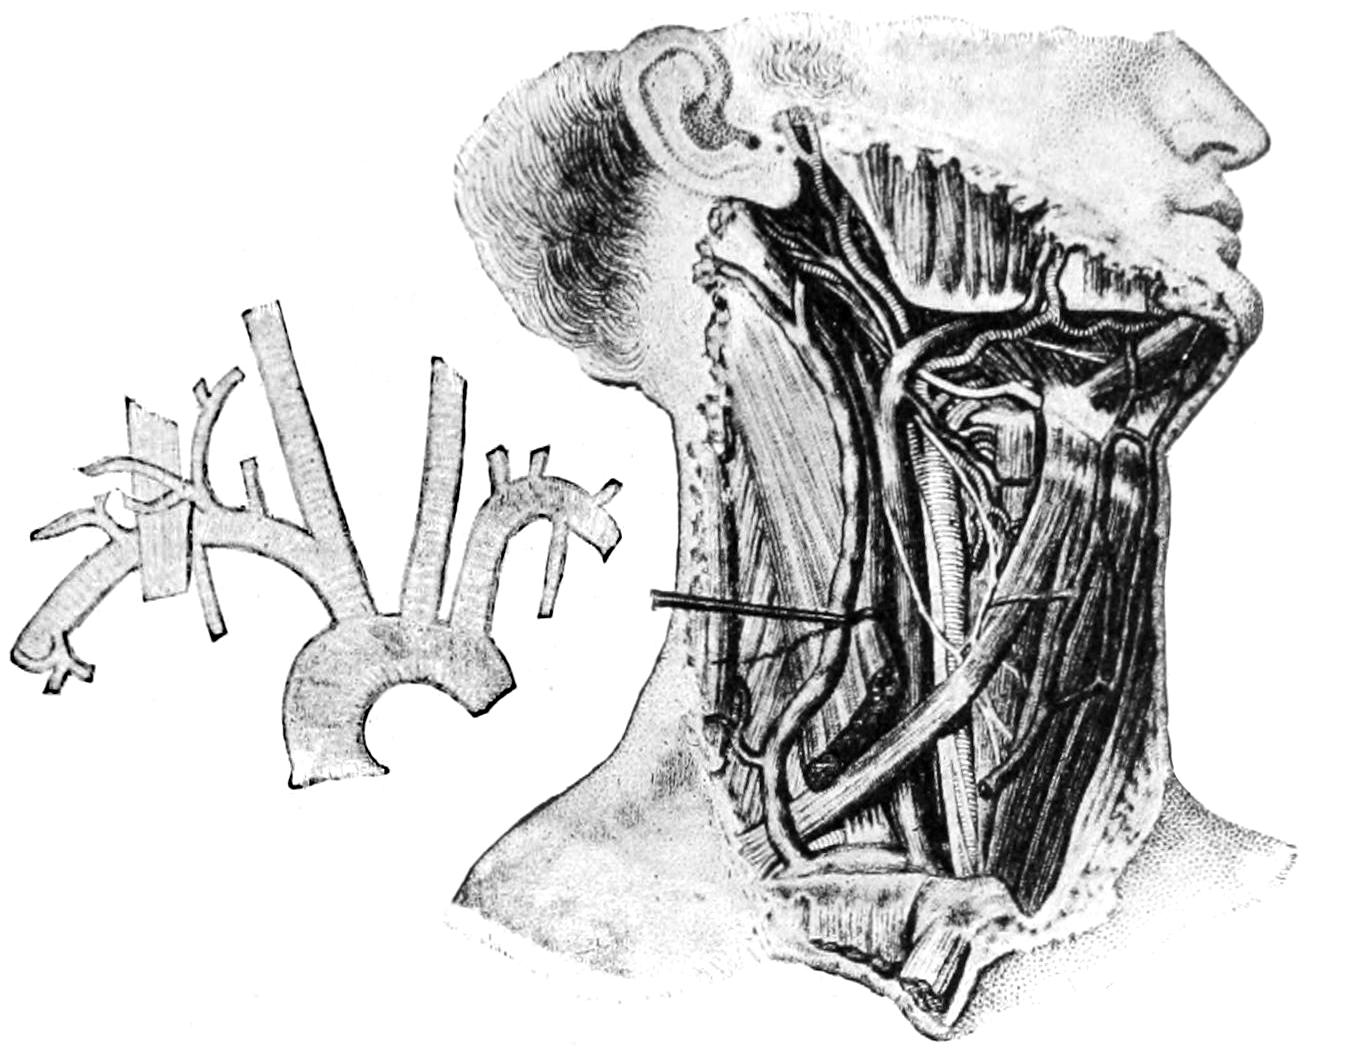

—Active hyperemia may be produced by purely nervous influences, even those of emotional origin. The flushing of the face which is known as “blushing” is, perhaps, the most common illustration of this fact. It is well known also that this is, in some degree at least, the result of division of certain nerves which have to do with the regulation of the blood supply. The cervical sympathetic is the best known and most often studied of these, and the consequences of division of this nerve in the neck are stated in all the text-books on physiology. So also by electrical stimulation of certain nerves the parts supplied by them can be made to show a very active hyperemia, which will subside shortly after discontinuance of stimulation, providing this has not been kept up too long. In active hyperemia there is absolute increase of intra-arterial tension, and under these circumstances pulsation may be noted in those small vessels in which commonly it is not seen nor felt. This is the explanation of the throbbing pain complained of under many actively hyperemic conditions. This hyperemia affords the explanation of the clinical signs to which attention has already been called. The increased heat of the part is the result of greater access of blood, which prevents cooling by radiation and evaporation; the peculiar redness is due to the greater filling of the capillaries with the blood, which gives the peculiar hue to the skin and visible textures; while to the increased pressure upon sensory nerves is also due the pain. The minuter changes occurring within the congested part call for more accurate description. Whether or not there is actual dilatation of capillaries under these circumstances is a matter still under dispute, but of the dilatation of the larger vessels there can be no possible question.

As hyperemia is to such a great extent brought about by action of the nervous system, it is well to divide it more accurately into the hyperemia of paralysis, or neuroparalytic congestion, which is the result of a paralysis of the constrictor fibers of the vasomotor system, and into the hyperemia of irritation, or neurotonic congestion, which is due to the irritation of the dilators (Recklinghausen). Physiologists are fairly well agreed that as between the dilating and the constricting apparatus of the vasomotor system there is ordinarily preserved a certain degree of equilibrium; to which fact is probably due that normal condition of affairs inaugurated after temporary disturbance, since overaction in one direction succeeds reaction in the other. As Warren has illustrated this, our common treatment of frostbite by cold applications is a concession to this fact, since by the cold applications we endeavor to limit the reaction which would otherwise follow after thawing out the frozen part.

The best examples of the hyperemia of paralysis are perhaps to be met with after certain injuries to nerves, as, for instance, flushing of the face and hypersecretion of nasal mucus, tears, etc., after injury to the cervical sympathetic. Such, too, in its essentials is that form of shock known as brain concussion, which is often followed by nutritive disturbances among the brain cells, with consequent perversion of brain function.